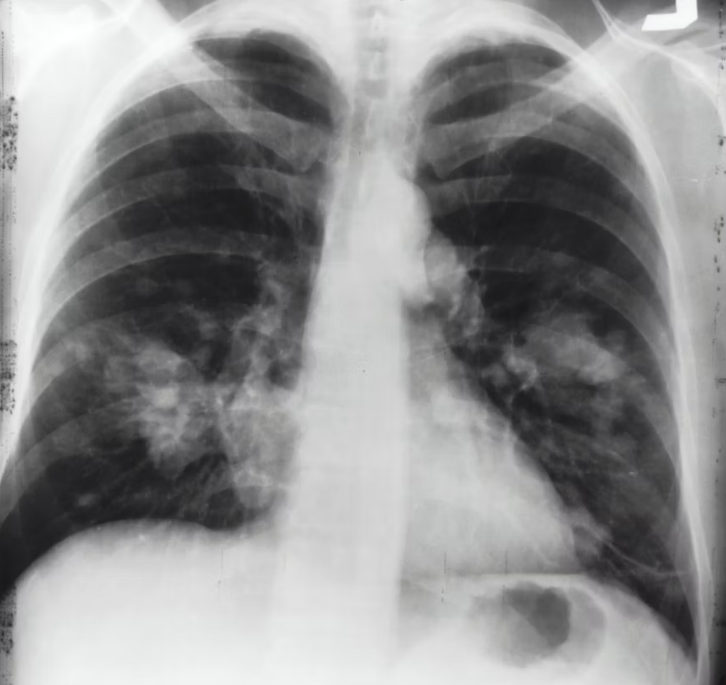

**폐기흉(肺氣胸, Pneumothorax)**은 폐 안의 공기가 새어 나와 흉강(가슴막 안쪽 공간)에 고이면서 폐가 압박을 받아 정상적으로 팽창하지 못하는 상태를 말합니다.

폐기흉은 젊은 층에서는 주로 체형(마른 체형)과 관련해 발생하지만, 중장년층에서는 폐 질환, 흡연, 노화로 인한 폐 기능 저하와 밀접하게 연결됩니다.

- 이차성 기흉

- 폐기종, 만성폐쇄성폐질환(COPD), 폐결핵 등 기존 질환이 있는 경우

- 중장년층에서 특히 위험